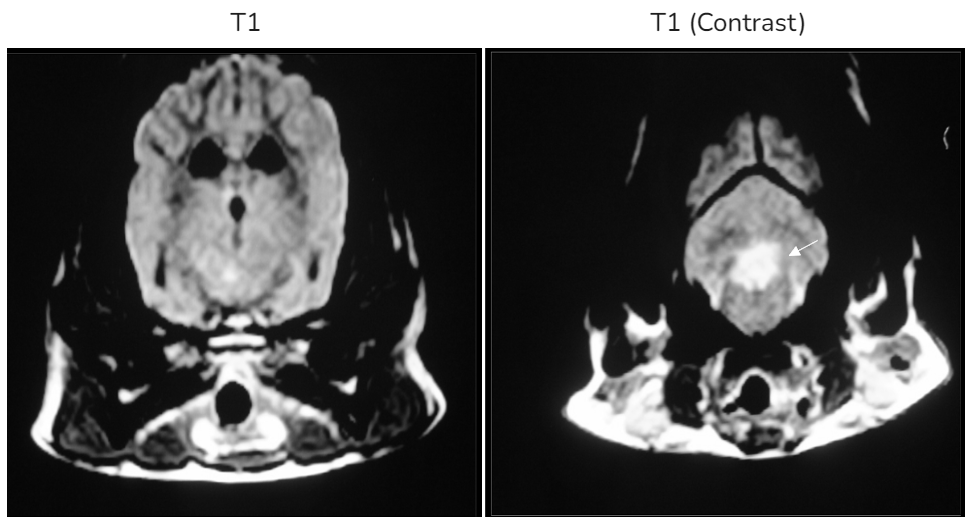

| CSF analysis |

![]() |

| - Color : ๋ง์(colorless) - Protein : >300mg/dL โ ๋์ ํธ - Nucleated cell count : >100cells/ฮผl โ ๋ฐฑํ๊ตฌ ์ฆ๊ฐ - Mononuclear pleocytosis (monocytes, lymphocytes ์ฆ๊ฐ) [2๋ฒ์งธ ์ฌ์ง] - Bacterial, fungal culture, Toxo, Ehrlichia : X |

| โ ๊ฐ์ผ์ฑ ์์ธ์ฒด X / ๋์ ์ผ์ฆ์ฑ ์นจ์ค ์กด์ฌ |